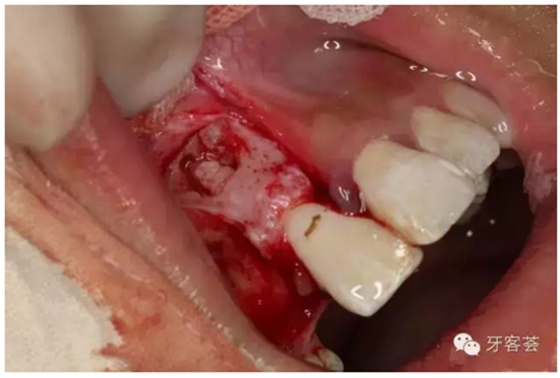

圖10:清理完成的12牙槽窩,并翻瓣暴露11的根尖區(qū)骨壁,骨壁完整、無破壞。

圖11:根據(jù)根尖片準(zhǔn)確定點(diǎn)根尖區(qū)位置、并用超聲骨刀去骨。

圖12:去骨、暴露11根尖區(qū).